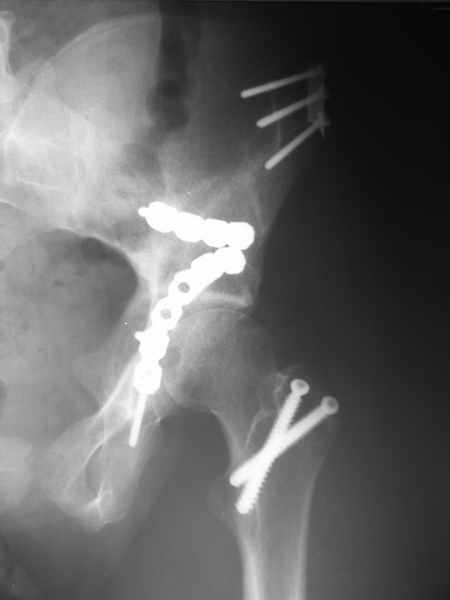

Посылаю схемы и 3D реконструкцию подобного повреждения. Называется он полным высоким двухколонным переломом вертлужной впадины, а "переломы крыла и тела подвздошной кости" входят в это понятие.

Вариантов остеосинтеза много (можно и не оперировть, т.к. конгруентность при таких переломах как правило сохраняется)

1 закрытая репозиция аппаратом + фиксация через проколы винтами

2 закрытая репозиция передней колонны + открытая задней колонны из задне-неружного доступа

3 открытая репозиция передней колонны из подвздошнго доступа + открытая задней колонны из задне-наружного доступа

4 открытая репозиция из илиоингвинального доступа

5 открытая репозиция из Y образного доступа

Я бы ориентировался на Y образный доступ

или из двух если есть сомнения в целостности задних отделов крыла.

прикладываю схему доступа и случай.

Одним задне наружным переднюю колонну не достать, а илио-ингвинальный более сложный не позволяет контролировать суставную поверхность и трудно управлять задней колонной.